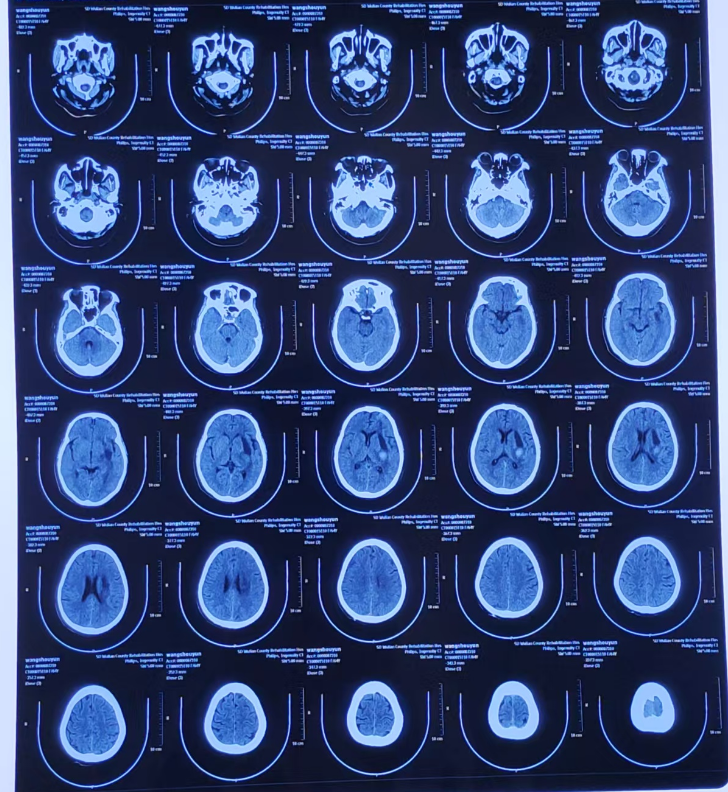

启动绿色通道!神经康复科、重症康复科、医学影像中心及临床检验科等多个科室现场会诊,立即给予止血、降压、静脉通道、呼吸机等紧急处理,颅脑CT显示左侧外囊区脑内血肿(致死致残高危区域)!医护人员争分夺秒展开急救!

术前CT显示脑血肿最大截面31.8mmx5.19mm

脑出血的黄金抢救时间一般在发病后的5分钟到6小时!神经康复科团队迅速评估病情,与家属沟通说明情况后,决定当天为患者实施改良立体定向颅内血肿穿刺引流术+XPER-CT引导手术。手术由神经康复科经验丰富的赵恒奎医师主刀,术中运用立体定向技术,在术中CT的引导下,通过专业定向仪准确定位穿刺部位,顺利引流出颅内血肿。

术中CT引导,精准定位

患者术后两周复查CT